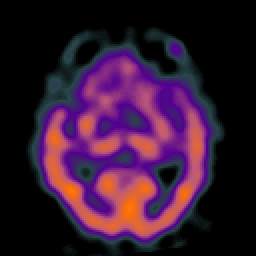

Alzheimer's Disease: SPECT/fMRI overlay -- Slice #4

[Home][Help][Clinical] Slice 4